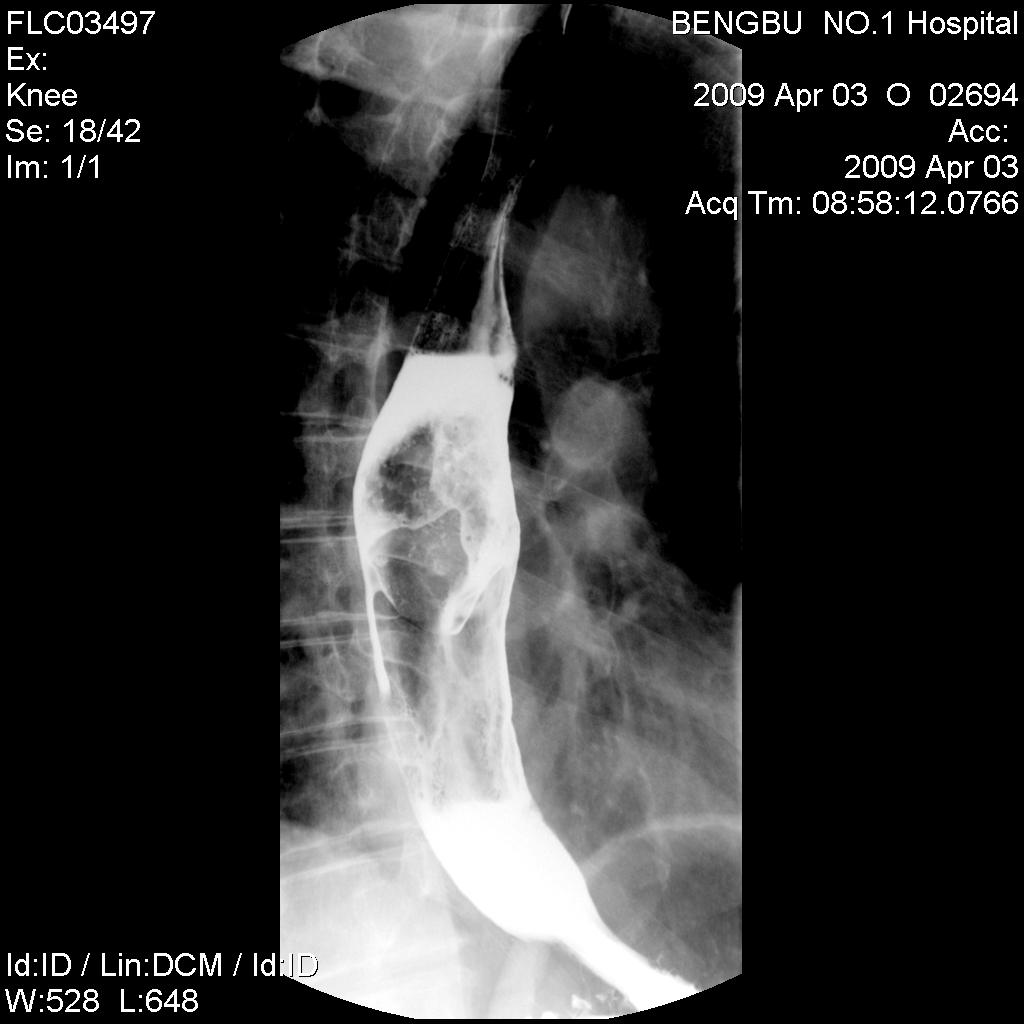

标题: X5565:男,50岁,吞咽阻塞感1月余。 [打印本页]

标题: X5565:男,50岁,吞咽阻塞感1月余。

食管中下段椭圆形充盈缺损,钡剂呈分流尚通畅,粘膜未见明显中断,其上段未扩张。初步考虑食管平滑肌瘤。曾有一病例影像表现类同,结果似为未分化癌。

食管中下段椭圆形充盈缺损,钡剂呈分流尚通畅,粘膜未见明显中断,其上段未扩张。初步考虑食管平滑肌瘤。

食管中下段椭圆形充盈缺损,边缘尚光滑,钡剂呈分流状通过块影,粘膜未见明显中断,管壁未见明显僵硬和缩窄改变。-----平滑肌瘤可能性大。

诊断:食管中下段椭圆形充盈缺损,边缘清晰光滑,肿块表面钡剂涂布征,似见细小龛影,钡剂分流改变,患段官腔扩张度及柔软度尚好,无明显僵硬及狭窄,上段以上食管未见明显扩张及钡剂储留,考虑食管平滑肌瘤,未除外溃疡性食道癌,建议食管镜活检。

肿块呈腔内膨胀性生长,边缘光滑

结果:食道癌。